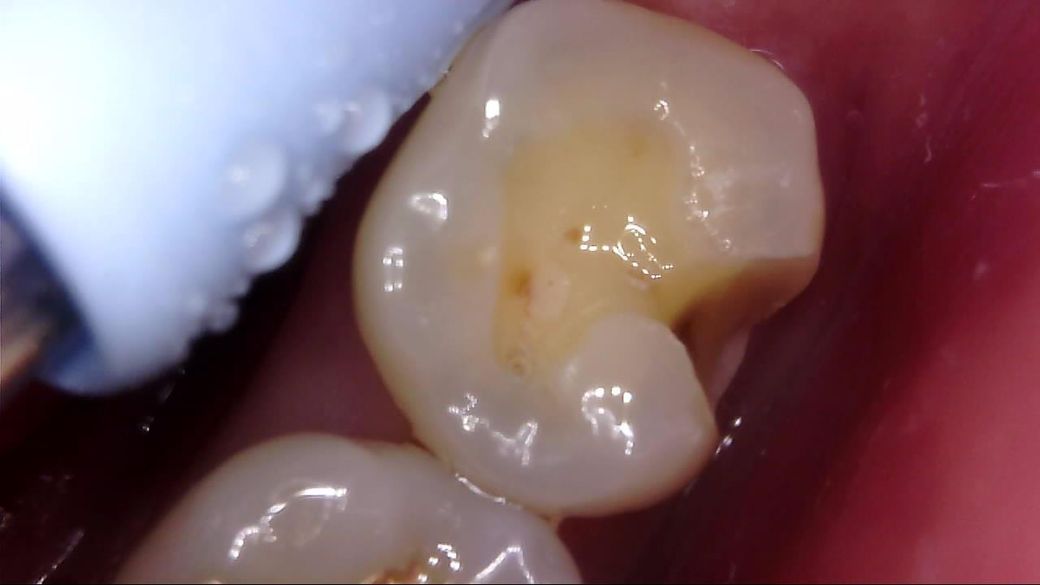

이차 우식이 상당히 깊게 발생하였는데, 치료 과정에서는 아래 사진과 같이 선생님께서 아래와 같이 일부 갈색 부분을 남긴 채 치아 삭제를 마치고 보철을 진행해 주셨습니다.

선생님께서는 "해당 부분은 착색 부위로, 이대로 덮어도 무방하다"라고 말씀 주셨고, 저 역시 더 이상 파고들어가면 신경치료가 예상되어 최선의 치료를 해 주셨다고 생각합니다.

• 1번 째 사진

사진에 보이는건 일단 착색과 2차 충치가 섞여 잇는거 같습니다. 충치를 제거하는 저스피드 기구로 제거를 해보기너 눌러 봐서 단단하면 충치가 아닙니다.

사진으로 보이는 부분은 충치에 어느정도 영향을 받은 부위는 맞습니다. 하지만 감염이 되어 있는것으로 보이지는 않습니다.

착색은 아니고 이환 상아질 남긴 것 같습니다 감염 상아질은 깔끔하게 다 제거 됐습니다